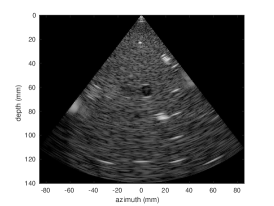

3.2 Results

Quantitative results for the cardiac test set are summarized in Table 1. We show a major improvement in decorrelation and SSIM for both and MLA. The corrected MLA performance approaches that of MLA, suggesting the feasiblity of larger MLA factors. Figure 4 shows representative images from each imaging modality. We show that the correlation coefficients profile of the corrected and MLA approaches that of SLA.

![]() |

|

| (a) SLA | (b) 5MLA | (c) Corrected 5MLA | |

||

| (d) 7MLA | (e) Corrected 7MLA |